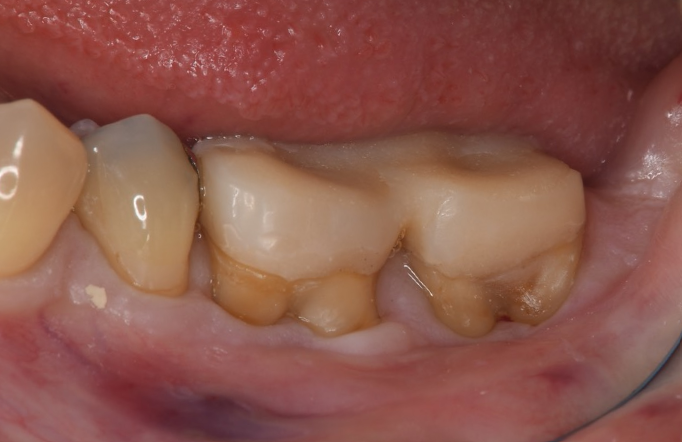

症例2

| 項目 | 詳細 |

|---|---|

| 患者様データ | 67歳 女性 |

| 来院時の主訴 | 「歯周病を治して一生自分の歯で食事を摂りたい。」 |

| 医院の診断 | 重度歯周病とう蝕 |

| 通院期間 |

1年6ヶ月 |

| 来院回数 | 10回 |

| 治療費 | 総額:480,000円(税抜) 歯周基本治療は保険適用診療 【内訳】 《保険適用診療》 歯周病検査・歯磨きや生活習慣指導・歯石取りクリーニング 《自費診療》 歯周組織再生療法240,000円(費用は範囲によって異なります。)、セラミック治療120,000円×2 |

| リスクと副作用 | メインテナンスが必要、正しい歯磨き習慣が必要不可欠 |

| ここがこだわりのポイント!☝ | 重度の歯周病の治療には長い治療期間がかかります。重症になるまでに時間がかかっている分、治るのにも時間がかかるからです。この症例の場合、患者様に頑張っていただいた結果、歯周ポケットが8mm→2mmに改善し、健康な歯周組織(骨・歯肉)を獲得することができました。 一生涯自分の歯で食事ができるよう、引き続きサポートを続けさせて頂きます!本当によく頑張って下さいました。お疲れ様でした! |